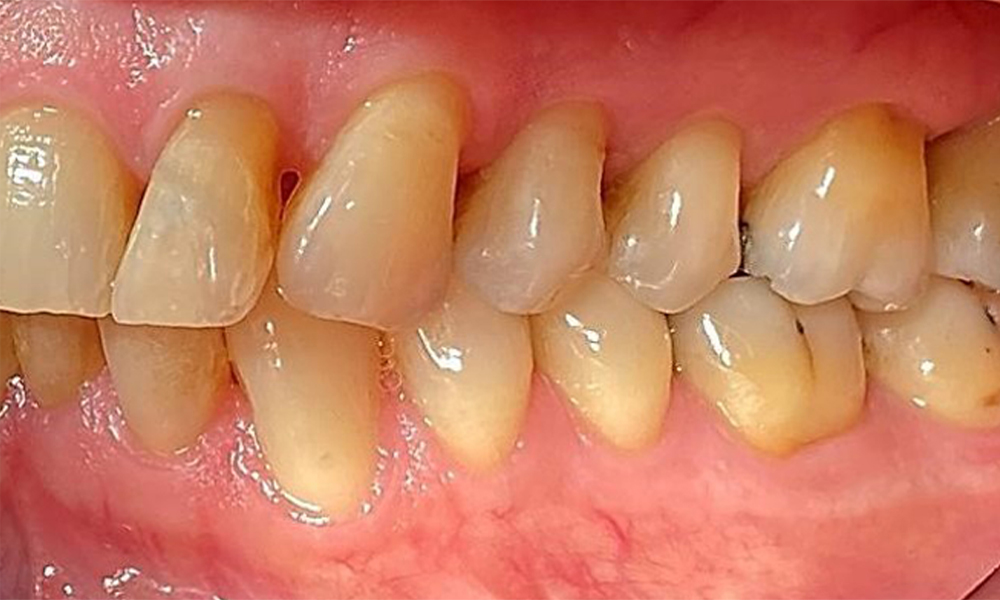

Lateralansicht links mit Ansicht der Rezessionen. © Dr. R. Krapf

Abb. 4 Lateralansicht links mit Ansicht der Rezessionen. © Dr. R. Krapf

Der Patient hat ein vollbezahntes Gebiss mit 28 Zähnen, an welchen sich im Molaren- und Prämolarenbereich Amalgamfüllungen und Compositefüllungen befinden. An Zahn 14 zeigt sich ein sichtbarer klinischer Randspalt. Zahn 27 hat ein suffizientes Goldinlay. Zudem zeigen sich generalisierte Attritionen und Abrasionen. (Abb. 2, Abb. 3, Abb. 4, Abb. 5, Abb. 6)

Der Patient hat eine Parodontitis Stadium II, Grad B (5). Die klinischen Sondierungstiefen liegen mit 1-3mm im physiologischen Bereich. Lokalisierte Sondierungstiefen finden sich an 17 und 27 jeweils mesiopalatinal mit 5mm. Es liegen generalisierte Rezessionen von 1-3mm vor mit partiellem Verlust der Interdentalpapillen (Abb. 2, Abb. 3, Abb. 4)